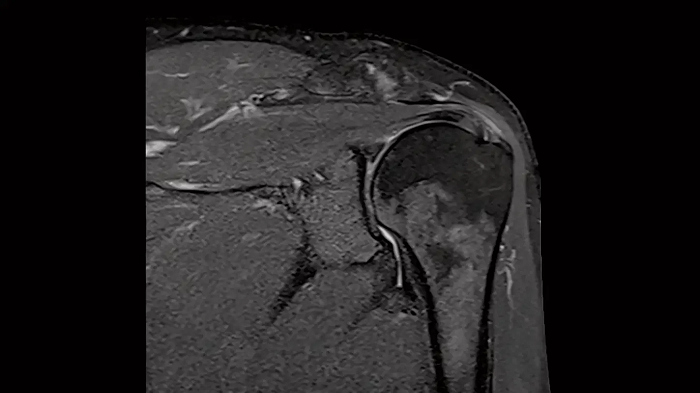

Shoulder

Shoulder - PD TSE FatSat

Exceptional fat suppression for the clear imaging of the shoulder.

Image Courtesy: University Hospital Erlangen, Germany | Image-ID: 4aaaa0384